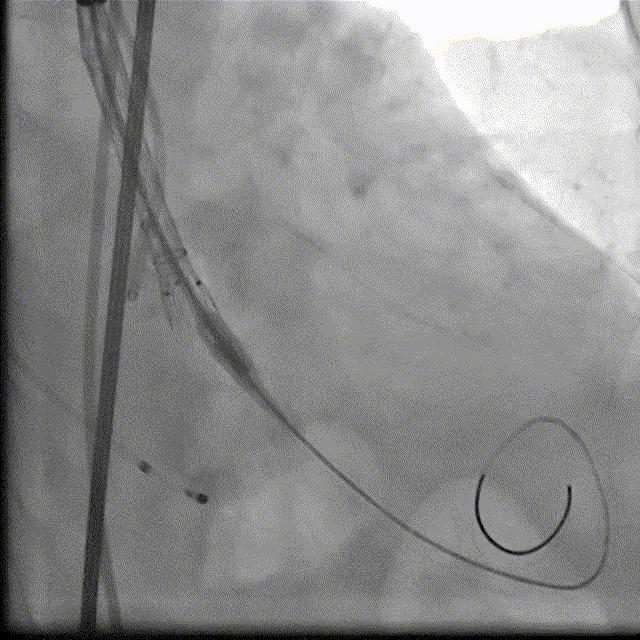

根部造影DSA

18球囊预扩DSA

瓣膜释放DSA

瓣膜最终形态